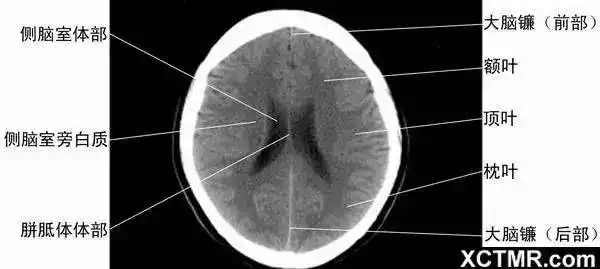

颅脑ct的正常解剖